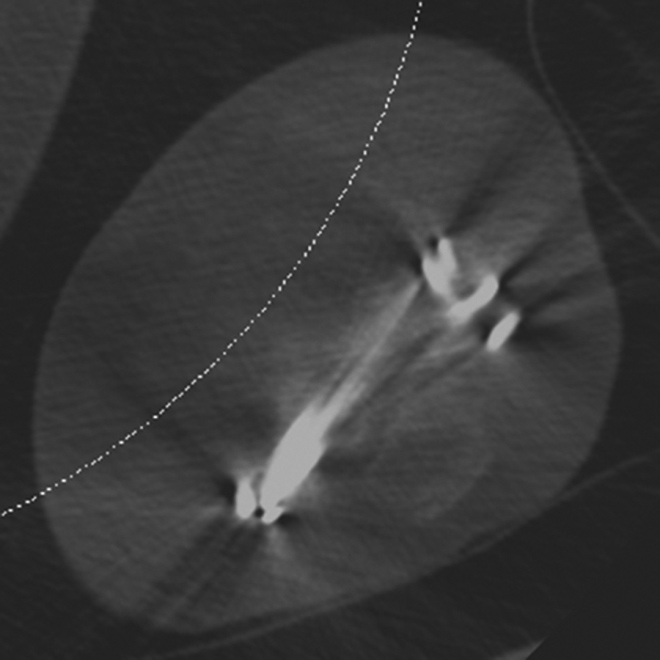

Hardware Failure. Sagittal multiplanar reformation demonstrates fractured pedicle screw in patient with treated vertebral compression fracture and sudden onset of worsening back pain.